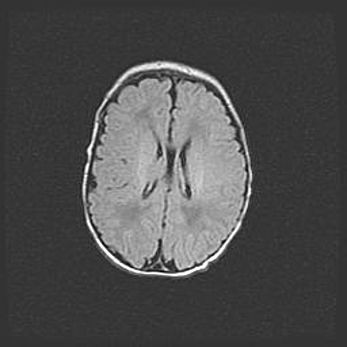

Сообщающаяся гидроцефалия. Кистозная энцефаломаляция головного мозга.

Возраст: 3 месяца 4 дня

Вес: 3100 г

Пол: женский

Окружность головы: 34 см

Срок гестации: 31 неделя

Кистозная энцефаломаляция головного мозга - одна из форм поражения головного мозга в детском возрасте. Характеризуется возникновением множественных и распространённых кист в коре, белом веществе и подкорковых образованиях головного мозга у плодов, новорождённых и детей раннего возраста. Развитие кистозной энцефаломаляции связано с внутриутробной асфиксией и гипотонией, родовой травмой, тромбозом синусов, пороками развития сосудов, инфекциями, сепсисом и другими причинами. Наиболее значимые инфекционные агенты: вирусы простого герпеса, цитомегалии, краснухи, токсоплазмы, энтеробактерии, золотистый стафилококк и другие.